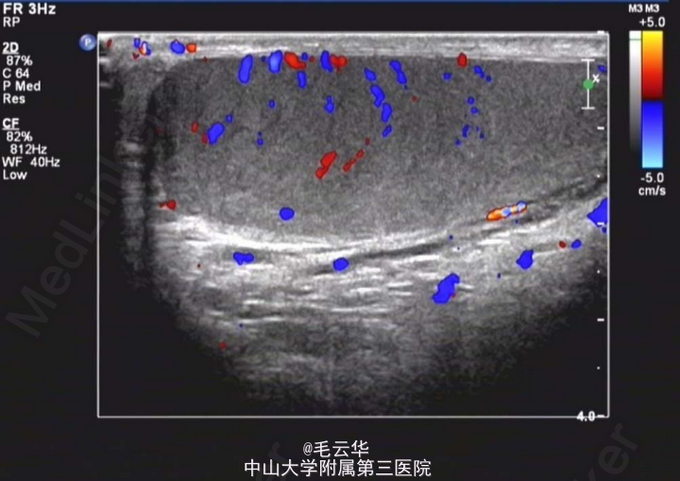

入院诊断:睾丸肿物性质待查 入院完善相关检查,尿常规:白细胞计数36.2个/ul↑;性激素六项:垂体泌乳素:1068.78 uIU/mL↑(48-375),雌二:164.56 pmon/L↑ (<146.1),睾酮14.77 nmol/L ↑ (0.5-2.6),促黄体生成素:1.87 uIU/mL ↓(3.1-34.6);血清人绒毛膜促性腺激素正常;CA199,CA125,CA153正常。阴囊超声检查结果示:右侧阴囊内实性肿块回声(120*71*68mm),边界清楚,内部回声不均匀,可见条索状高回声,考虑睾丸来源肿瘤性病变可能。左侧睾丸超声检查未见明显异常。 左侧附睾超声检查未见明显异常。肝、胆、胰、脾、肾、输尿管、膀胱、腹腔淋巴结超声检查均未见明显异常。MR示:右侧阴囊内占位,考虑睾丸来源恶性肿瘤,精原细胞瘤可能大。行右侧睾丸切除术,标本送病理。术后病理显示右侧睾丸肿物精原细胞瘤;“切缘”未见肿瘤。术后患者拒绝对同侧髂淋巴结和腹膜后淋巴结进行预防性放疗,嘱定期返院随访,办理出院。出院诊断右侧睾丸精原细胞瘤。